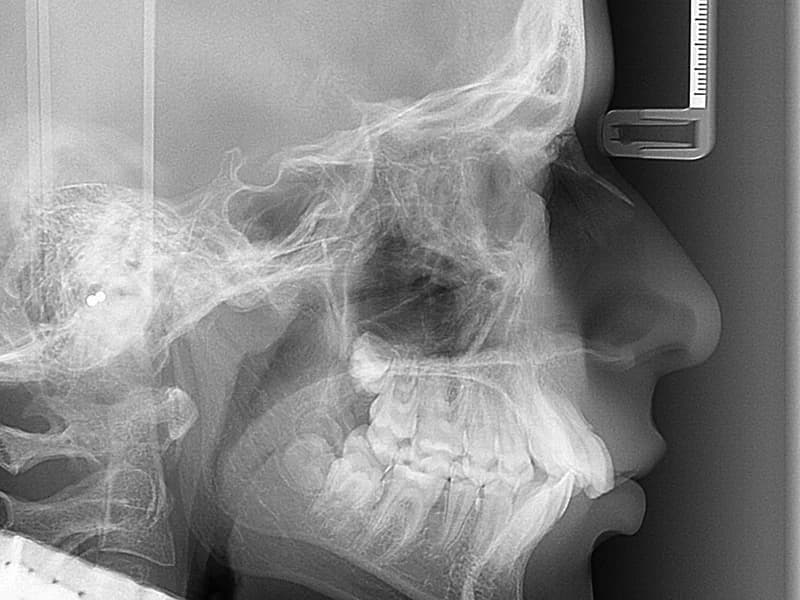

- –Kraniogram L-L ili P-A(Snimka nužna za ortodontsku terapiju. Prikazuje cijelu lubanju i odnos kostiju lica, koristi se za određivanje skeletalne klase i kefalometrijsku analizu.)